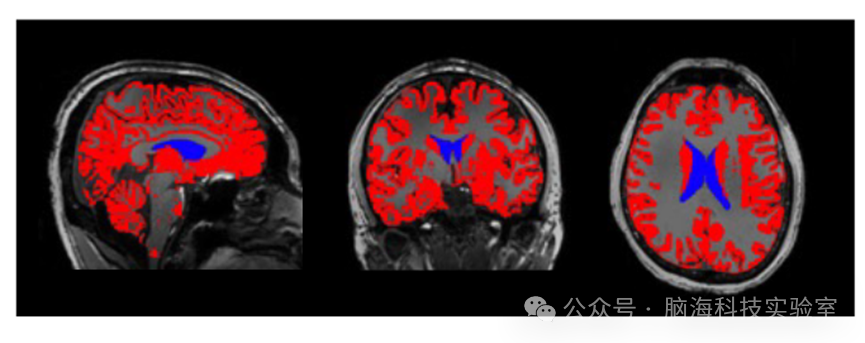

脑部 MRI 图像,侧脑室以蓝色涂成,脑室充满脑脊液。